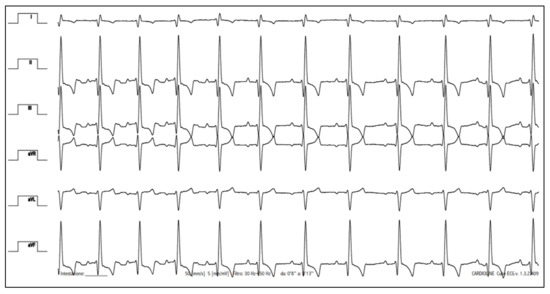

Case Description and Clinical Investigations

- Romito, G.; Cipone, M. Deep and huge transient negative T waves in dogs with myocardial injury. J. Vet. Cardiol. 2021, 36, 131–140. [Google Scholar] [CrossRef]